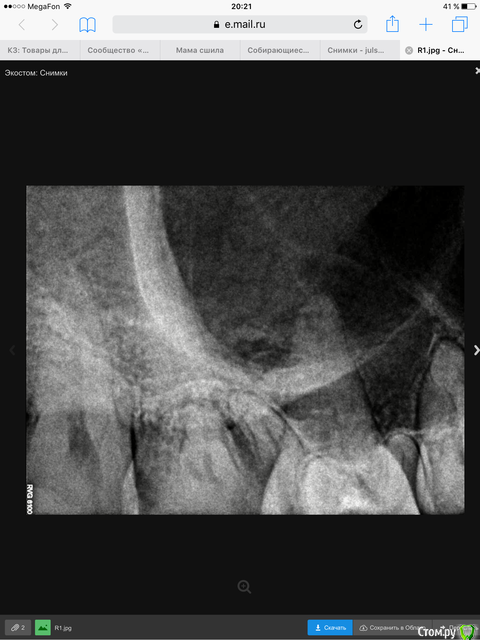

Julsvs Опубликовано 30 марта, 2016 Автор Поделиться Опубликовано 30 марта, 2016 Вот как смогла сфотографировала. 1 Ссылка на комментарий

Julsvs Опубликовано 13 мая, 2016 Автор Поделиться Опубликовано 13 мая, 2016 Вот КТ( проблема в правой шестерке). Другого снимка нет- выдали результаты на диске. Ссылка на комментарий

DmitrySH Опубликовано 27 мая, 2016 Поделиться Опубликовано 27 мая, 2016 На последнем снимке у 7 зуба хорошо видны щечные корни, вот сделайте тоже самое у 6-го Ссылка на комментарий

Julsvs Опубликовано 28 мая, 2016 Автор Поделиться Опубликовано 28 мая, 2016 Вот порыталась.https://goo.gl/photos/R2KvywgJmZjvb2Ju7 Ссылка на комментарий